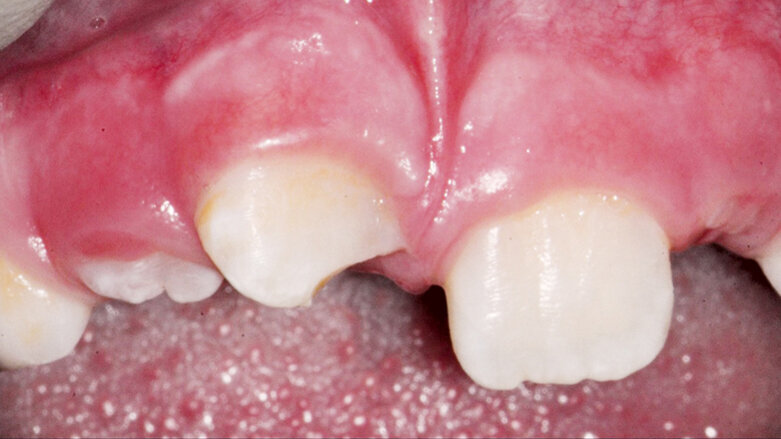

Stav před endodontickým ošetřením (Fotografie: MUDr. Hana Zallmannová)

Endodontické ošetření zubů s nedokončeným vývojem představuje v endodoncii zvláštní výzvu. Zatímco u laterálních zubů je příčinou nekrózy pulpy zpravidla kaz, u frontálních zubů to bývá úraz.

Postupy běžně používané pro ošetření zubů s dokončeným vývojem kořene nelze použít. V současnosti se nabízí tři metody: